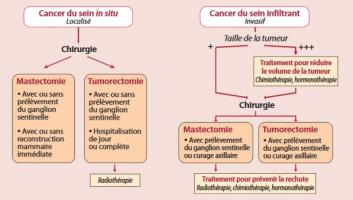

Actualité publiée il y a 3 années 4 moisCANCER du SEIN : Le traitement, une question d'offre de soins autant que de protocole